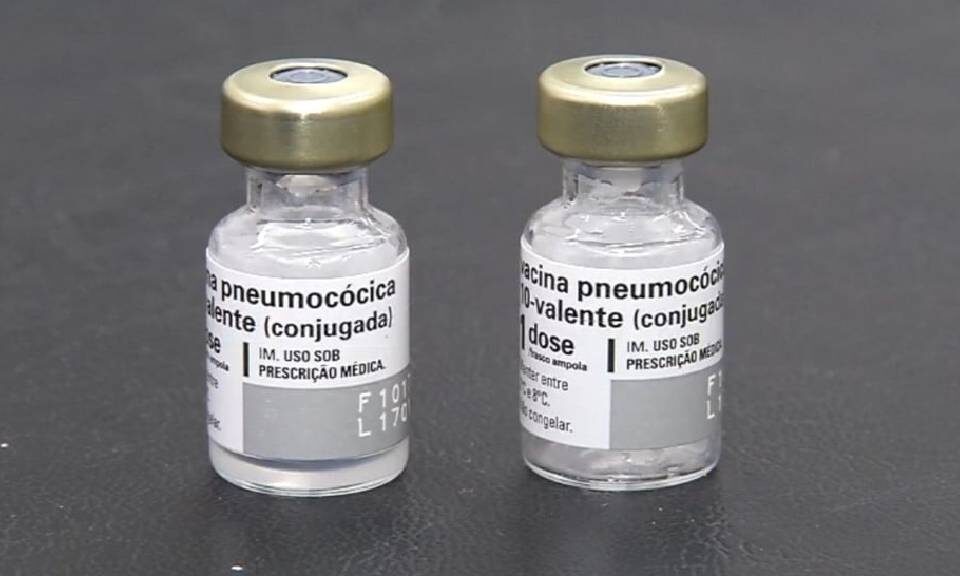

O Espírito Santo tem registrado uma retomada na excelência da cobertura vacinal para crianças menores de dois anos. Em 2023, as vacinas com metas preconizadas pelo Ministério da Saúde mostraram um aumento progressivo em relação aos anos anteriores, e a tendência de crescimento continua em 2024. O sistema de informação Vacina e Confia tem desempenhado um papel crucial nesse avanço, junto com a participação das famílias.